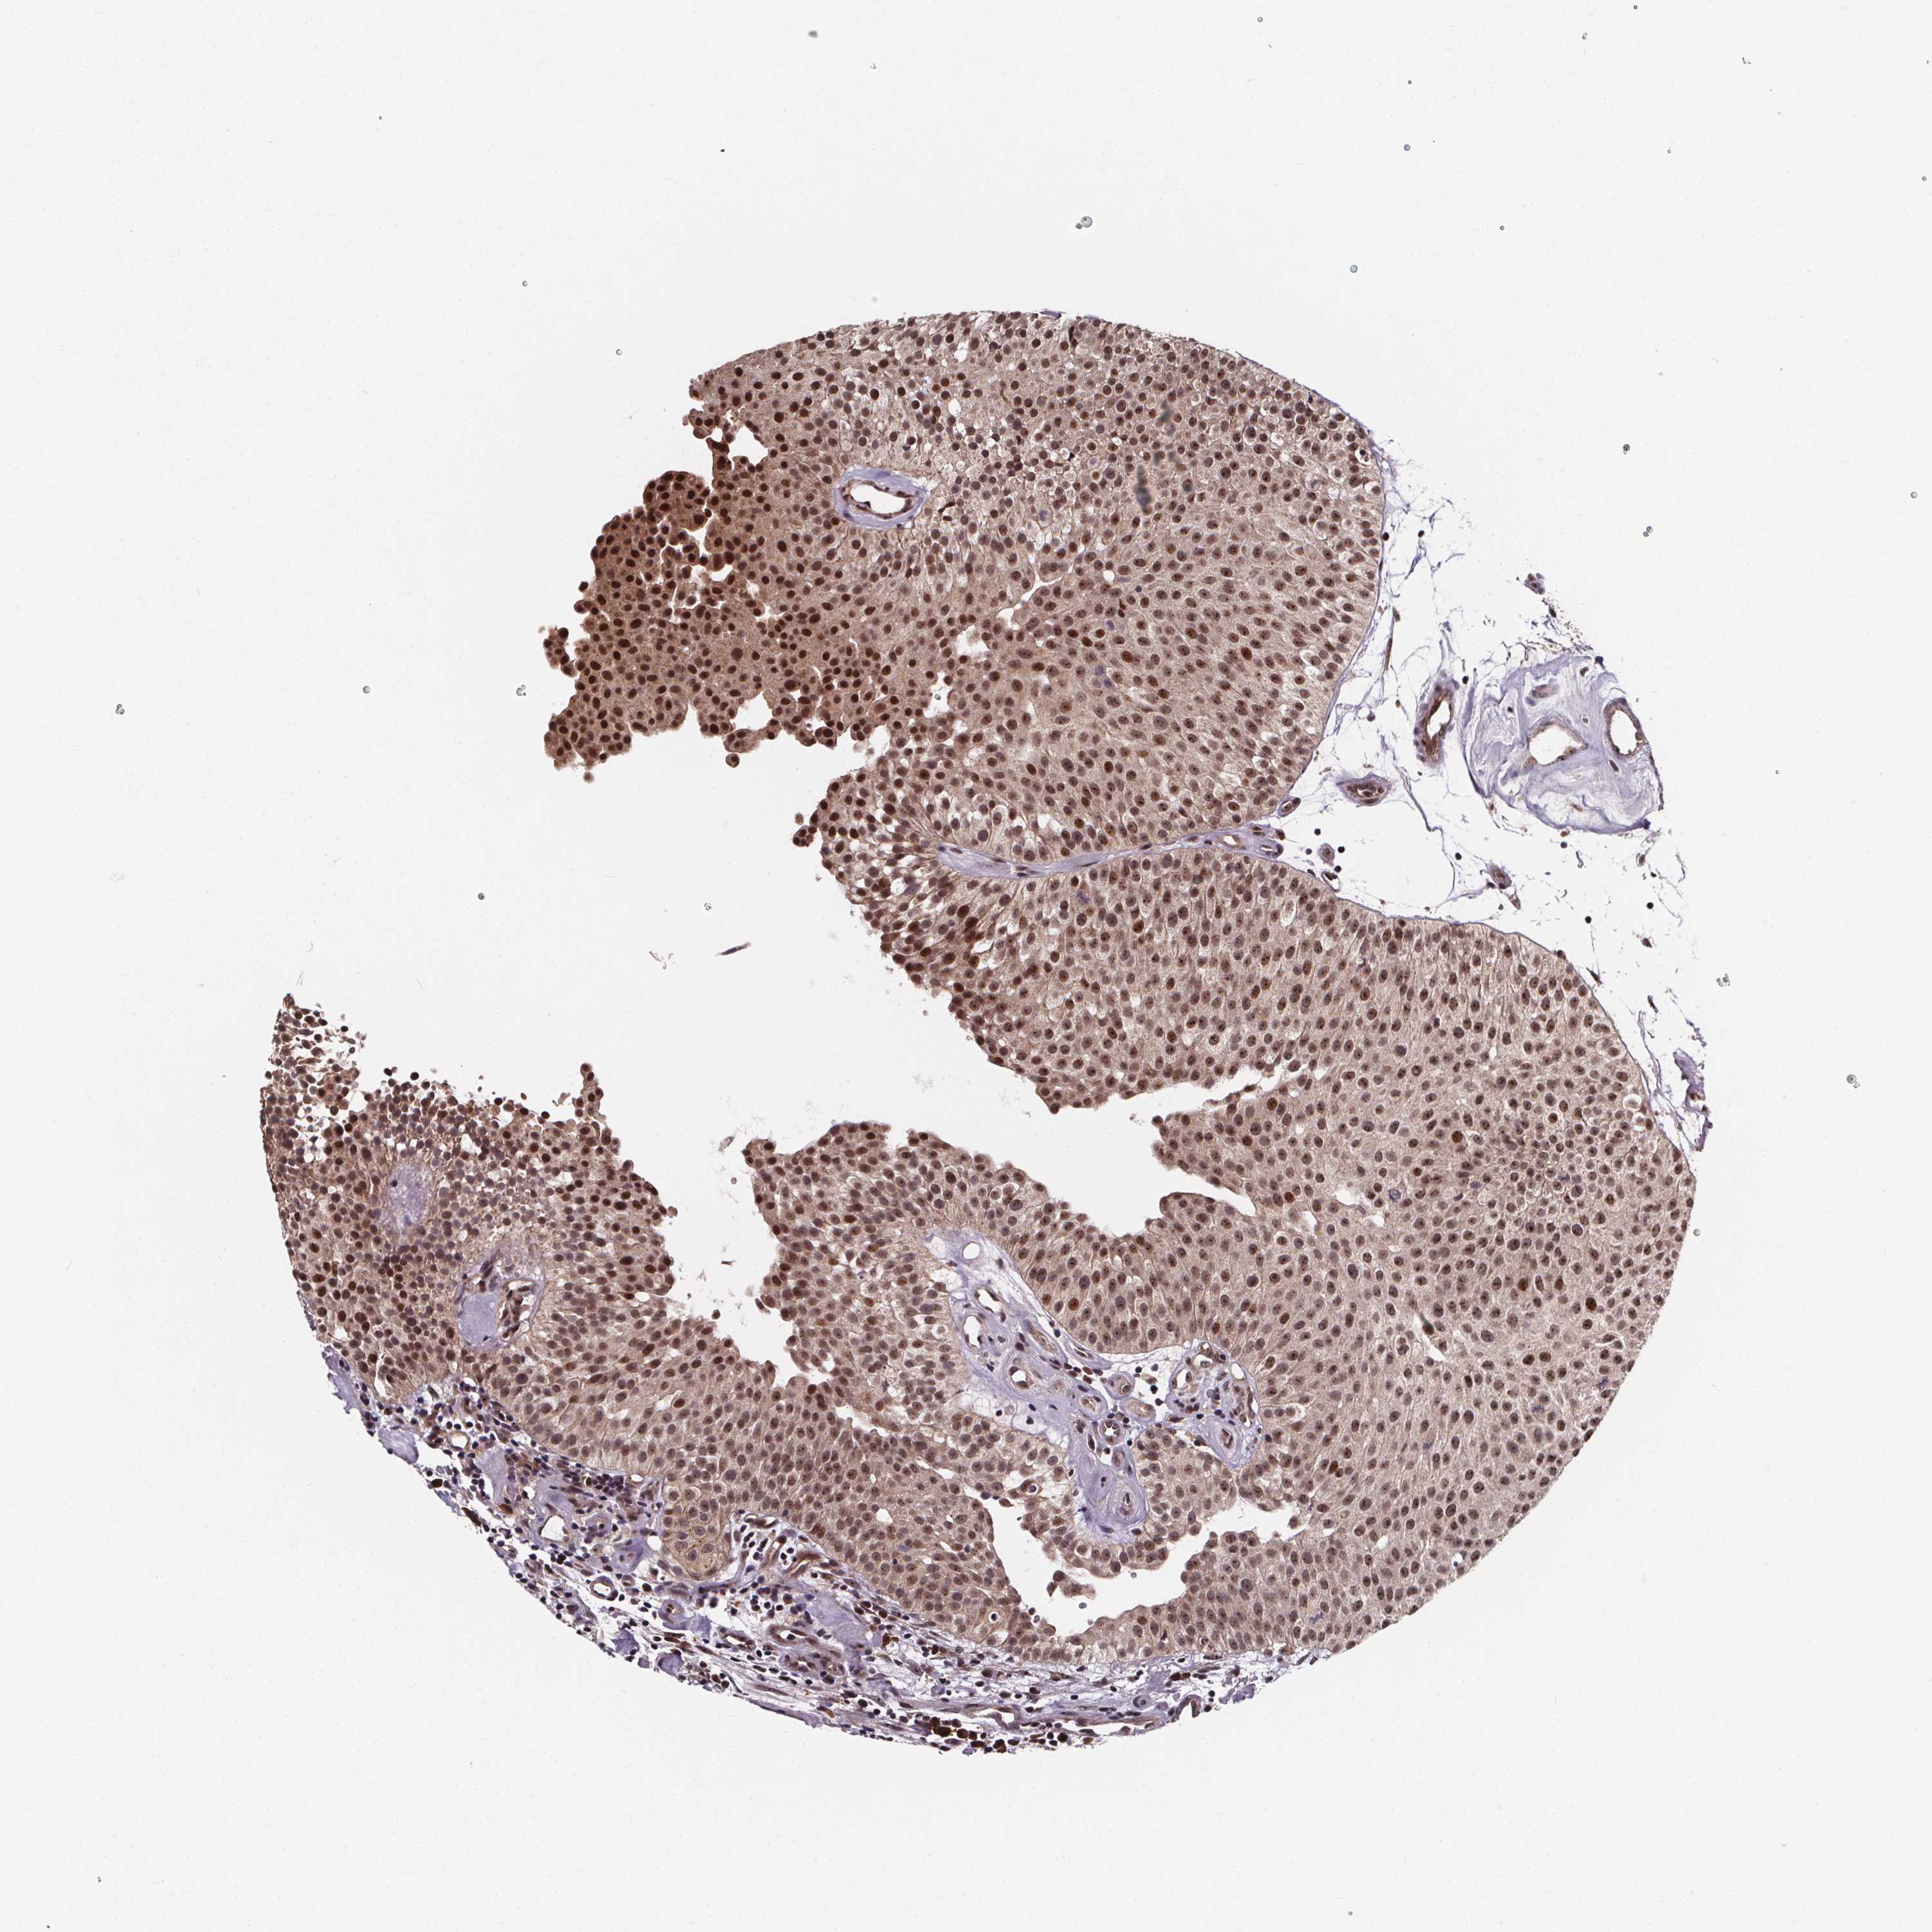

UROTHELIAL CANCER - Protein expressioni

A mouse-over function shows sample information and annotation data. Click on an image to view it in a full screen mode. Samples can be filtered based on level of antibody staining by selecting one or several of the following categories: high, medium, low and not detected. The assay and annotation is described here.

Note that samples used for immunohistochemistry by the Human Protein Atlas do not correspond to samples in the TCGA dataset.

Antibody stainingi

Antibody staining in the annotated cell types in the current human tissue is reported as not detected, low, medium, or high, based on conventional immunohistochemistry profiling in selected tissues. This score is based on the combination of the staining intensity and fraction of stained cells.

Each image is clickable and will lead to virtual microscopy that enables deeper exploration of all samples and also displays staining intensity scores, fraction scores and subcellular localization as well as patient and tissue information for each sample.

Antibody HPA068416

Staining

High

Medium

Low

Not detected

Intensity

Strong

Moderate

Weak

Negative

Quantity

>75%

75%-25%

<25%

None

Location

Nuclear

Cytoplasmic/membranous

Cytoplasmic/membranous,nuclear

Urothelial carcinoma, High grade

Urothelial carcinoma, NOS

Urothelial carcinoma, Low grade